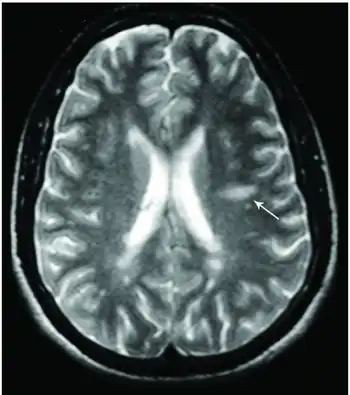

![]() Dawson's Fingers appearing on an MRI scan |

This morphologic appearance was named Dawson's fingers by Charles Lumsden, after the Scottish pathologist James Walker Dawson,[31] who first defined the condition in 1916.

Dawson's fingers

"Dawson's fingers" is the name for the lesions around the ventricle-based brain veins[32][33] of patients with multiple sclerosis and antiMOG associated encephalomyelitis[34]

Though once thought to be specific of MS, it is known not to be the case.[35]

The condition is thought to be the result of inflammation or mechanical damage by blood pressure[30] around long axis of medular veins.

Dawson's fingers spread along, and from, large periventricular collecting veins, and are attributed to perivenular inflammation.[36]

Lesions far away from these veins are known as Steiner's splashes.[30]